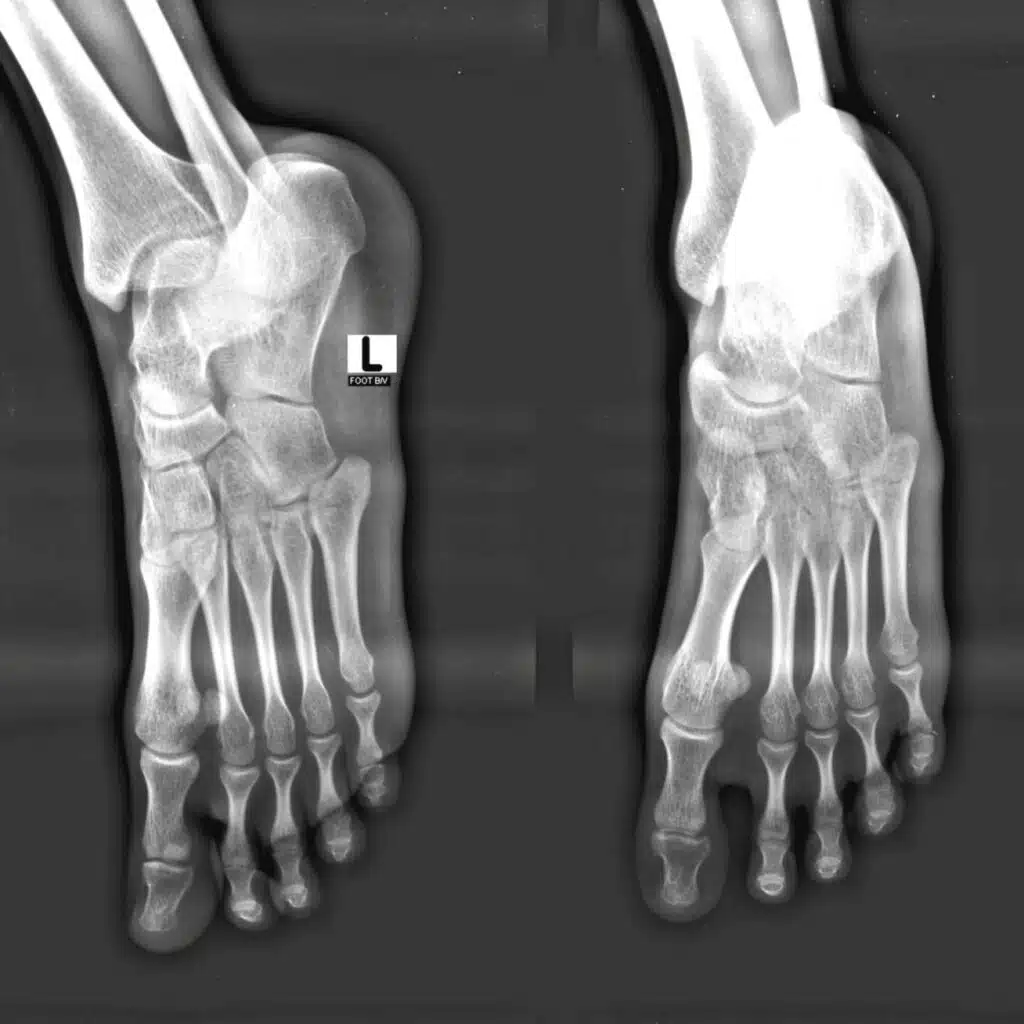

• Abnormal Foot Structure: Individuals with flat feet (excessive pronation) or a valgus deformity (where the heel angles outward) are more susceptible. These structural issues can stretch and compress the tibial nerve over time.

• Trauma or Injury: A previous ankle sprain or fracture can lead to inflammation and swelling within the tunnel, causing nerve compression.

• Space-Occupying Lesions: Benign growths such as varicose veins, ganglion cysts, or bone spurs can take up space within the tarsal tunnel and impinge on the nerve.